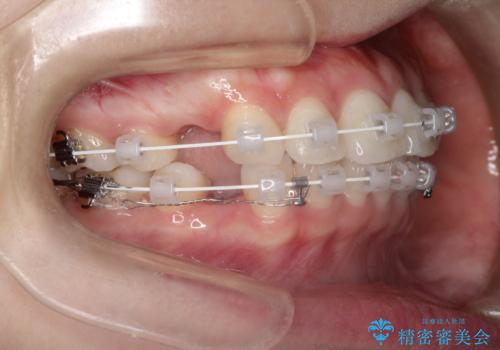

口が閉じにくい 口ゴボの抜歯矯正による改善

- 審美装置

- 2年1ヶ月

- 口が閉じずらく、口元が出ていることを主訴に来院されました。

上下左右の歯を1本ずつ抜歯して、そのスペースを利用して口元を引っ込める計画としました。